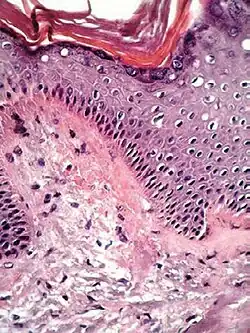

| Lichen planus | Irregular epidermal hyperplasia with a jagged “sawtooth” appearance, compact hyperkeratosis or orthokeratosis, foci of wedge-shaped hypergranulosis, basilar vacuolar degeneration, slight spongiosis in the spinous layer, and squamatization. The dermal papillae between the elongated rete ridges are frequently dome shaped. Necrotic keratinocytes can be observed in the basal layer of the epidermis and at the dermal-epidermal junction. Eosinophilic remnants of anucleate apoptotic basal cells may also be found in the dermis and are referred to as “colloid or civatte bodies”. Whickham striae are usually seen in the areas of hypergranulosis. Vacuolar degeneration at the basal layer may be noted leading to focal subepidermal clefts (Max Joseph spaces). Squamatization occurs as a result of maturation and flattening of cells in the basal layer. It happens in areas of marked hypergranulosis with prominence of the sawtooth pattern of rete ridges. Wedge-shaped hypergranulosis can occur in the eccrine ducts (acrosyringia) or hair follicles (acrotrichia). In the hypertrophic subtype, the associated hyperkeratosis, parakeratosis, hypergranulosis, papillomatosis, acanthosis, and hyperplasia markedly increased with thicker collagen bundles forming in the dermis. Moreover, the rete ridges are more elongated and rounded as opposed to the typical sawtooth pattern. In atrophic LP, loss of the rete ridges and dermal fibrosis is prominent. In vesiculobullous LP, the disease progression is quicker. Hence, some of the distinctive features such as hyperkeratosis, hypergranulosis, or dense lymphocytic dermal-epidermal infiltrate may not be present. LP lesion may resolve with residual hyperpigmentation caused by a persistent increase in the number of melanophages in the papillary dermis.[9] | ![]() |

|